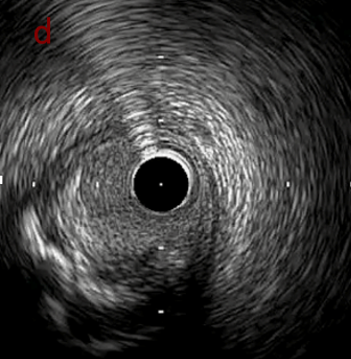

IVUS after OAS high speed 3回

IVUS imaging after high speed 3回

a,b,cはさらに石灰化に食い込み、石灰化量は減少。

それに伴いdではbiasがさらにtentingのIVUS所見にへんかしhigh injury riskと思われた。

引き続き造影で確認してpinpointで引きのOAS high speedを3回さらに追加のためcでIVUSマーキングを行い、その点より引きで赤線のpinpoint OAS high speedを行い、dに関してはinjury回避のためにOASを当てない方針とした。